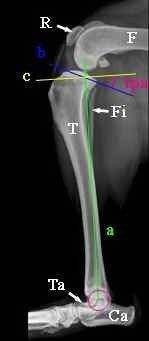

- Les traitements chirurgicaux dans la prise en charge de la dysplasie de la hanche images qui permettent d’améliorer le pronostic locomoteur du chien ainsi que sa qualité de vie.

- Les chirurgies réparatrices lors de fractures des membres avec utilisation de broches, plaques et vis.